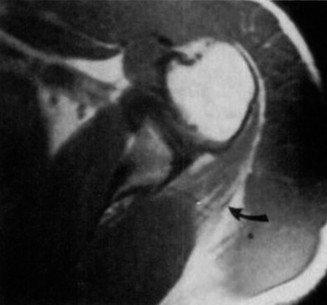

Identify the muscles that compose the force couples in the transverse and coronal planes? CASE 3 A 35-year-old male has had left shoulder pain for 4 months, ever since a low-speed motor vehicle accident (MVA). Physical examination demonstrates preserved range of motion but pain and some weakness with Jobe’s testing. His imaging is shown in Figure 2–8.

Figure 2–8_Reproduced with permission from Stadnick ME. _Partial Rotator Cuff Tears. MRI Web Clinic. 2007 (Apr).

What is the most likely diagnosis?

The correct answer is (A). These are best diagnosed on an MRI as seen in the imaging provided; addition of intra-articular contrast can further improve this study. Answer B, full-thickness rotator cuff tear, is incorrect as the bursal side of the tendon can be seen to be in continuity. Answer C, a SLAP lesion, will be visualized as a labral tear on a coronal MRI and will be found at the biceps root. Answer D, an ALPSA lesion, will be most clearly seen on an axial MRI. It is a variant of a Bankart lesion where the labrum is displaced medially and inferiorly rolling down the glenoid neck underneath the periosteum.

MRI remains the most popular imaging modality for diagnosing rotator cuff tears. Normal rotator cuff tendon appears dark on both T1 and T2 sequences. Tears may be noted as being full-thickness, articular-sided, bursal-sided, or intrasubstance. They are visualized as a disruption in the regular contour of the tendon and increased signal intensity on T2 sequences. Occasionally, an MR arthrogram may provide additional information regarding a cuff tear, although this is not routinely ordered.